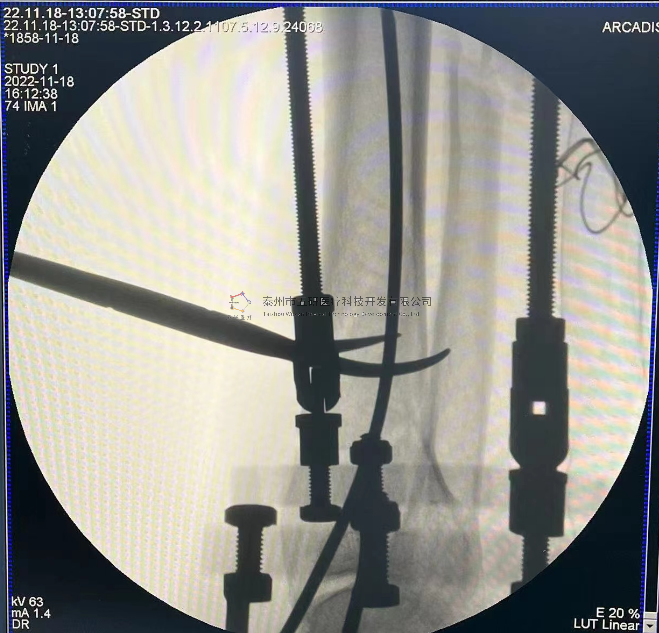

【影像圖片—術(shù)后】

【手術(shù)資料】